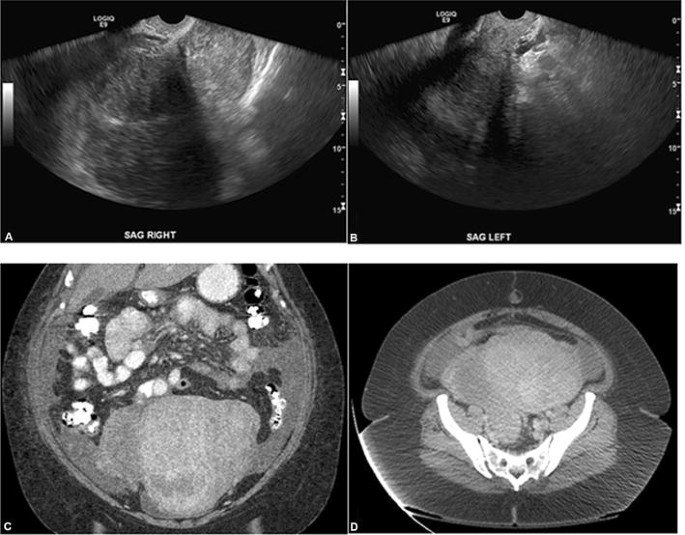

If the ovaries are not visualized, a doctor may order an ultrasound to get a better view of the ovaries. An ultrasound can help the doctor to identify any abnormalities in the ovaries, such as cysts or tumors. The ultrasound may also help to identify the cause of the non-visualization, such as endometriosis or adhesions.

In some cases, the ovaries may be too small to be seen, or they may be hidden behind other structures in the pelvis, such as the uterus or bowel. If this is the case, a different type of scan, such as an MRI or CT scan, may be required to view the ovaries.